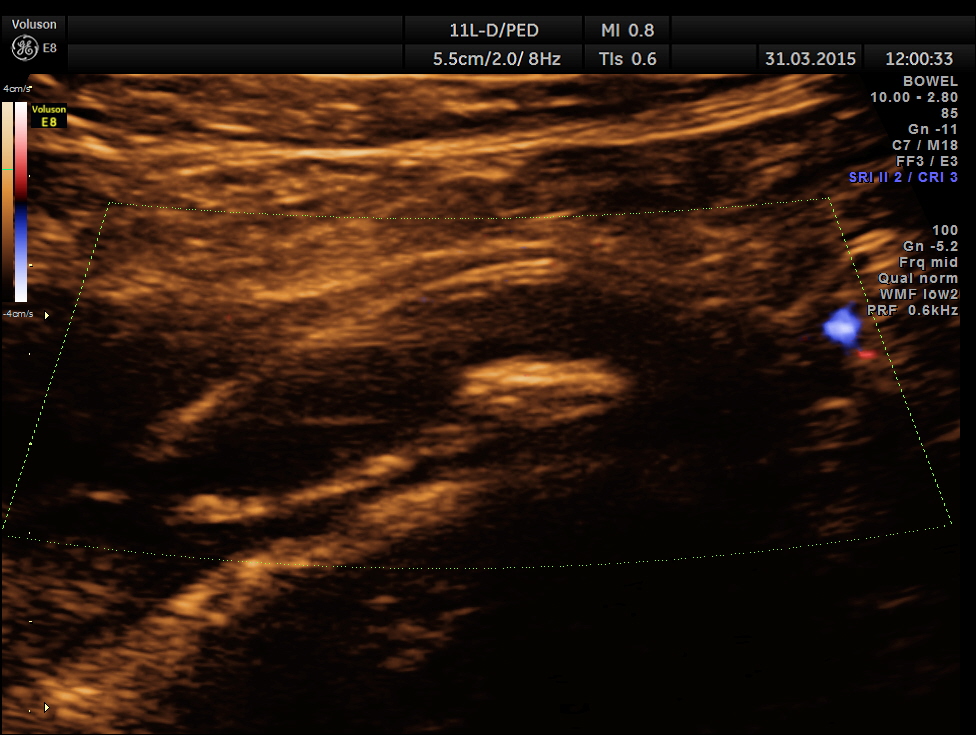

Ultrasound showed the following.

Scan ( with a regular abdominal probe ) over RIF shows an echogenic object with posterior acoustic shadowing within a dilated ” tube ” .

Colour Doppler shows vascularity of the wall . It was non pulsatile and non collapsible.

The following pictures are with a high resolution probe.

The following picture shows the long and short axis views.